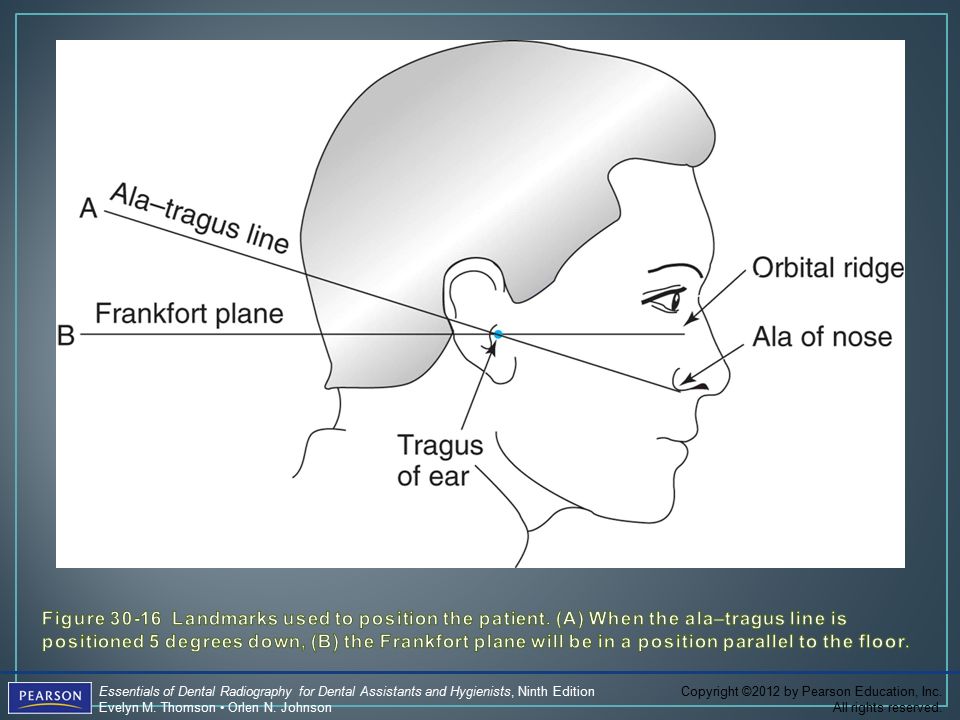

Ala tragus line panoramic. Ikfanson hing university of alabama scho. An imaginary plane or line from the orbital ridge to the acoustic. An imaginary plane or line from the ala of the nose. The roots of the anterior teeth are in the image and the posterior teeth are the same size on each.

This position is often referred to as the patient being positioned with the ala tragus line in a minus 50 position. At the same time this position allows the ala tragus line to be correctly positioned. The panelipse panorex i and panorex ii use the ala tragus line for patient positioning. Notice the panoramic image is divided into 9 areas that make up the 6 zones that you must learn to picture each panoramic radiograph or image in your mind s eye.

Tragus of the ear must be aligned with the plastic guides ala tragus line should be 50 from level positioning the patient position the patient panoramic lead apron must be used position apron high in front to protect the thyroid apron should be lower in back to expose the neck. Discussion most panoramic x ray machines use the ala tragus line for patient positioning whereas a few use the orbito meatal line. Ala tragus line is one of the common extra oral soft tissue land mark utilized in dental clinics for occlusal plane orientation. Here the occlusal plane should be mildly curved upward to make a smile like line.

The ala tragus line as a guide for orientation of the occlusal plane in complete dentures 1carole abi ghosn 2carla zogheib. The smile line will also be lost. An imaginary plane or line from the ala of the nose to the tragus of the ear. The part of a panoramic x ray machine where the cassette is positioned for exposure.

The angle between this line and the horizontal plane is 3on the panorex and 4on the. Focal trough layer that area between the x ray source and the image receptor that will be imaged distinctly on the panoramic. In other words the ala of the nose should be slightly inferior to the height of the tragus. These zones are as follows.

Important in determining the correct position of the patient s head. Exposure was 80 to 90 kv at 10 ma for 1 5 to 2 seconds in accordance with the subject s physical. The panorex i s. To achieve the correct vertical angulation the head must be positioned upright and symmetrical with the ala of the nose just inferior to the height of the tragus.